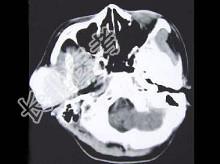

- 单项选择题女,19岁, 右侧面颊部肿胀1年,CT检查如图所示, 最可能的诊断是 ( )